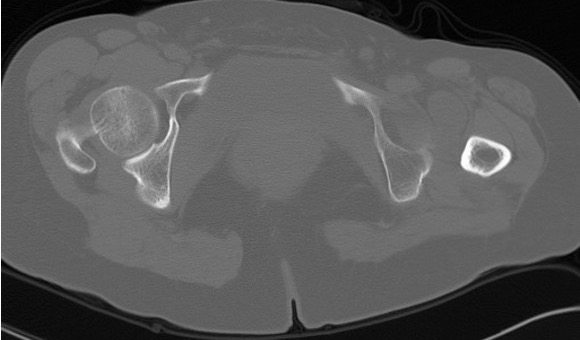

Crowe Classification

| Crowe Type | Definition |

|---|---|

| I | Subluxation < 50% vertical diameter femoral head |

| II | Subluxation 50 - 75% vertical diameter femoral head |

| III | Subluxation 75 - 100% vertical diameter femoral head |

| IV | Proximal migration of > 100% vertical diameter femoral head |

Crowe I

Crowe II

Crowe III

Crowe IV